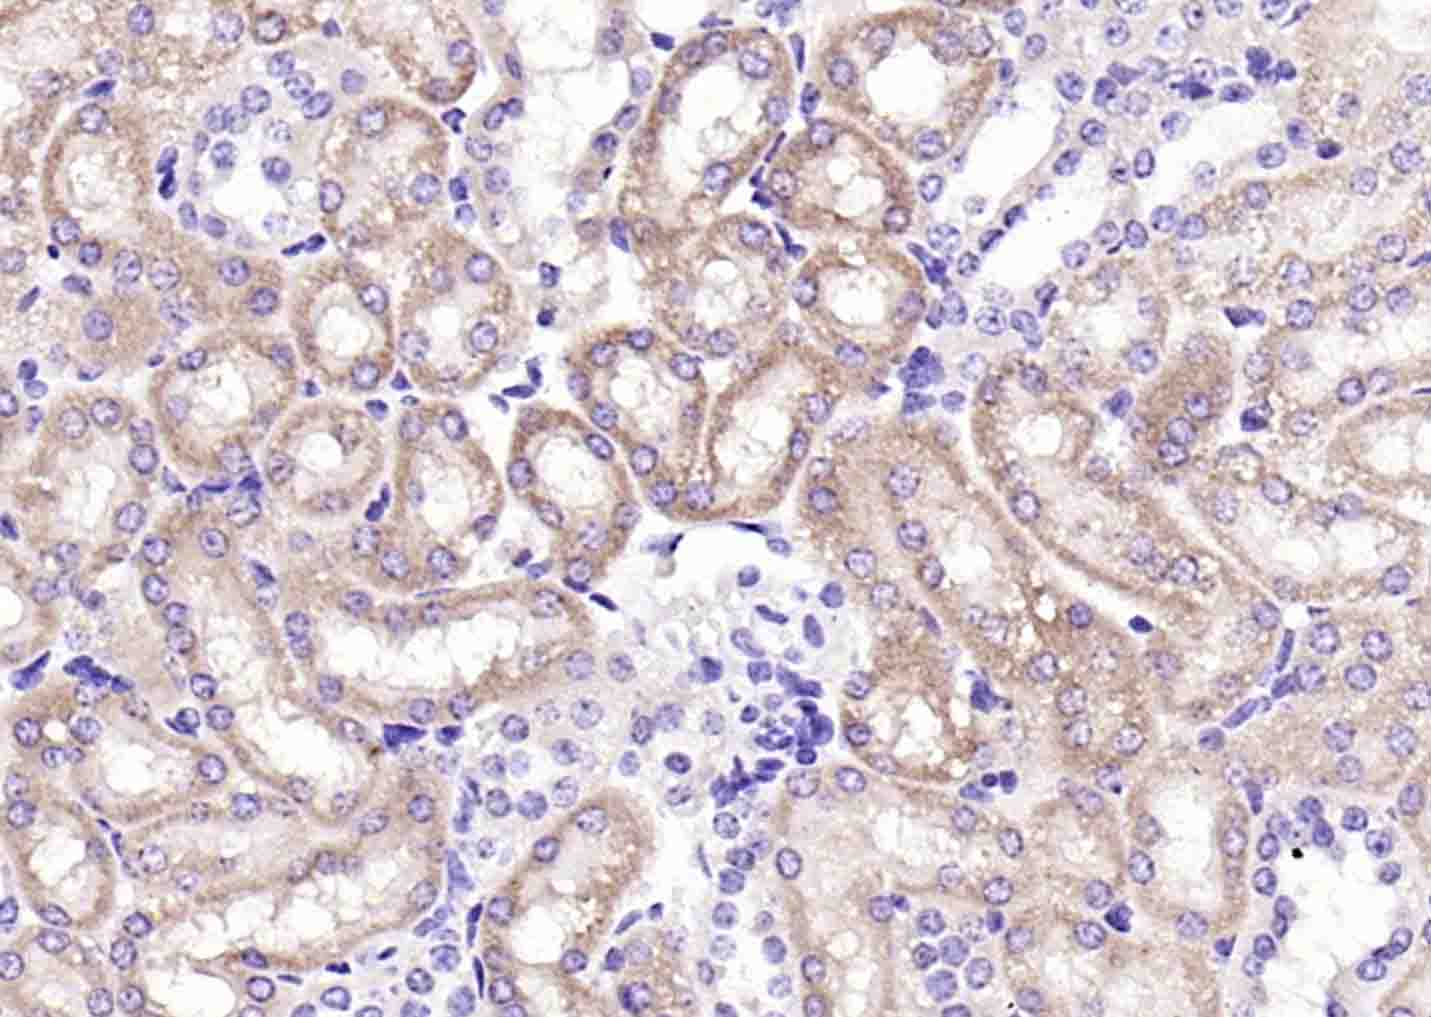

Paraformaldehyde-fixed, paraffin embedded (mouse kidney); Antigen retrieval by boiling in sodium citrate buffer (pH6.0) for 15min; Block endogenous peroxidase by 3% hydrogen peroxide for 20 minutes; Blocking buffer (normal goat serum) at 37°C for 30min; Antibody incubation with (IREB2) Polyclonal Antibody, Unconjugated (bs-4484R) at 1:200 overnight at 4°C, followed by operating according to SP Kit(Rabbit) (sp-0023) instructionsand DAB staining.

Paraformaldehyde-fixed, paraffin embedded (human kidney); Antigen retrieval by boiling in sodium citrate buffer (pH6.0) for 15min; Block endogenous peroxidase by 3% hydrogen peroxide for 20 minutes; Blocking buffer (normal goat serum) at 37°C for 30min; Antibody incubation with (IREB2) Polyclonal Antibody, Unconjugated (bs-4484R) at 1:200 overnight at 4°C, followed by operating according to SP Kit(Rabbit) (sp-0023) instructionsand DAB staining.